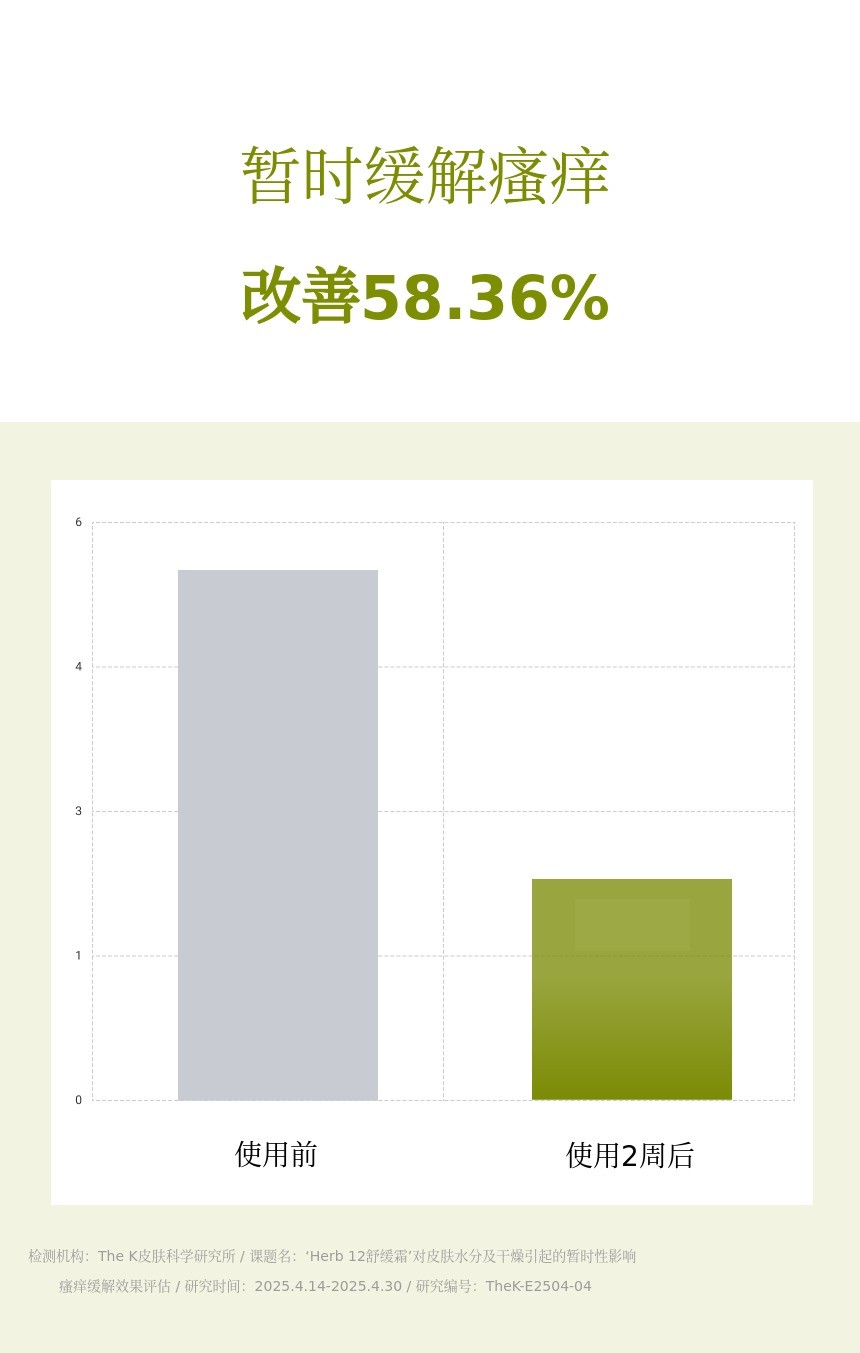

![[瘙痒改善58%]每日4克,两周后不再抓挠!草本舒缓霜](https://cdn3.wadiz.kr/studio/images/2025/06/17/f1750fad-9ffc-43e3-b1d4-8ecd97474d44.jpeg)